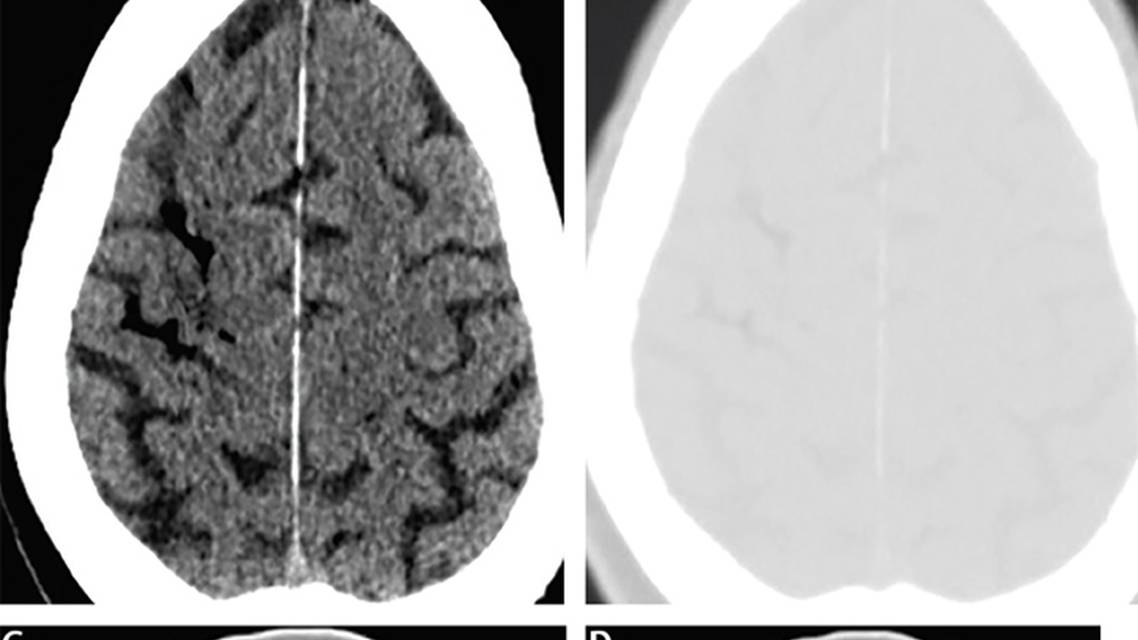

Diagnosis is made with head and brain CT and is indicated by hyperlucency that appears the same on both brain and bone windows (see Figure). Accurate diagnosis is essential because treatment of air emboli is time dependent as described in the case and following section.